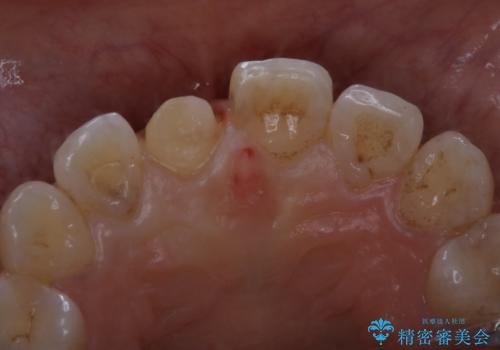

- プラスチックで治療している前歯が何度も欠けてしまうとお悩みで来院された方です。

歯全体を覆うクラウンにて治療を行いました。

前歯1本のみの被せ物治療を行う場合、他の歯を参考に歯の色や形を忠実に再現することが重要です。オールセラミッククラウン(スペシャル・エクセレント)は、事前に歯科技工士との打ち合わせを行うことで、歯の色や形、さらには患者様のご希望も聴取したうえでクラウンを作製することが可能です。